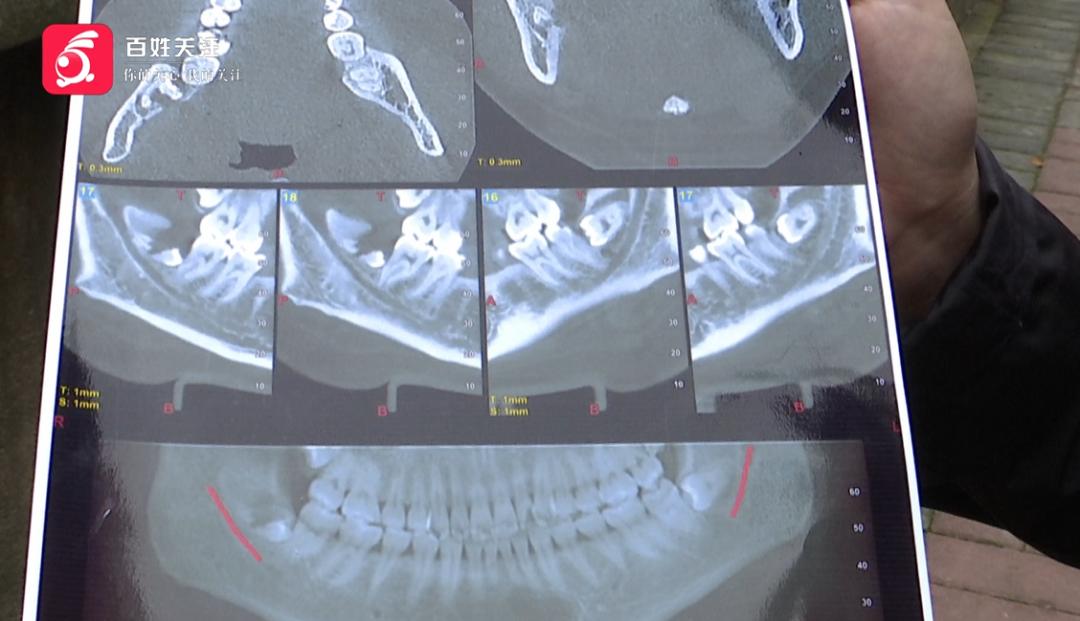

羅女士:復(fù)診才發(fā)現(xiàn),當(dāng)時(shí)拔的智齒沒有拔干凈,還有一半多殘留在里面,這個(gè)必須把它清理出來的。

圖片

應(yīng)該全拔掉的智齒

還剩半截不說

更讓羅女士氣憤的是

因?yàn)檫@次拔牙

她的舌側(cè)骨壁等結(jié)構(gòu)

也受到了影響

羅女士:從片子上來看,牙齒沒拔出來,還有一半。

記者:損傷怎么看出來?

羅女士:你看這邊是好的,骨頭還在,這邊骨頭斷裂了

。